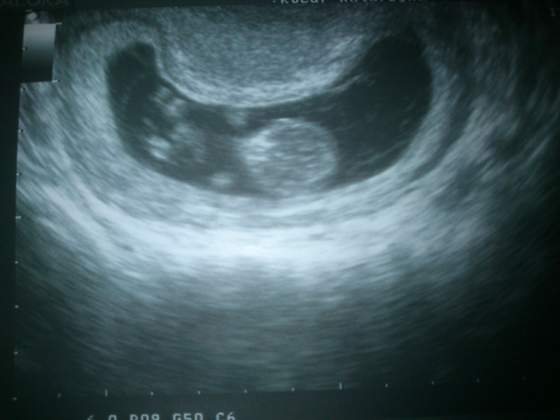

A to moj dzidzius zwiniety w fasolke - ale ruszal sie bo doktorkowi tetno uciekalo hehe